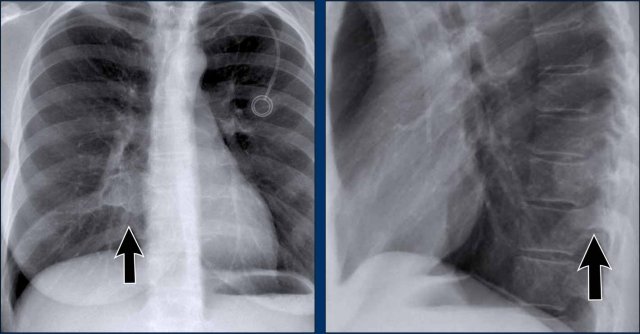

Left Atrial Enlargement

• Patient with a history of chronic mitral valve disease and valve replacement.

• Extreme dilation of the LA leads to bulging of both the right upper cardiac contour (black arrows) and posterior heart border on lateral view (blue arrow).

Right Ventricular Enlargement

First study the PA and lateral chest film and then continue reading.

Findings

• Chest radiographs show massive cardiomegaly, predominantly due to right ventricular dilation (yellow arrow on lateral view).

• Small aortic knob (blue arrow), with dilation of the pulmonary trunk and right lower pulmonary artery.

• Findings suggest a left-to-right shunt with secondary pulmonary hypertension.